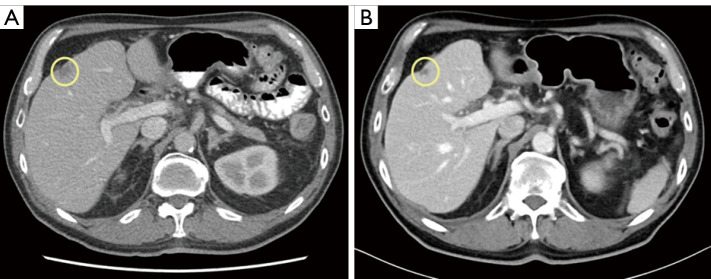

Case description: A 75-year-old gentleman with preexisting multivessel CAD was diagnosed with metastatic gastroesophageal junction (GEJ) squamous cell carcinoma (SCC) after presenting to medical attention with a 2-month history of worsening chest pain in addition to progressive dysphagia associated with weight loss. Following initial treatment with palliative locoregional radiotherapy to the lower mediastinum, GEJ, and upper abdomen, the decision was made to proceed with palliative systemic therapy. Considering his significant cardiac history, 5-FU was replaced with raltitrexed and combined with carboplatin and pembrolizumab. After a total of 10 months of treatment, the patient presented to hospital with recurrent chest pain and was diagnosed with a non-ST-elevation myocardial infarction (NSTEMI). Despite radiographic evidence of stability of his malignancy on systemic therapy, he was not considered to be a candidate for cardiac intervention. He was thus transitioned to a comfort-focused care approach and passed away shortly thereafter, with the cause of death being acute coronary syndrome.